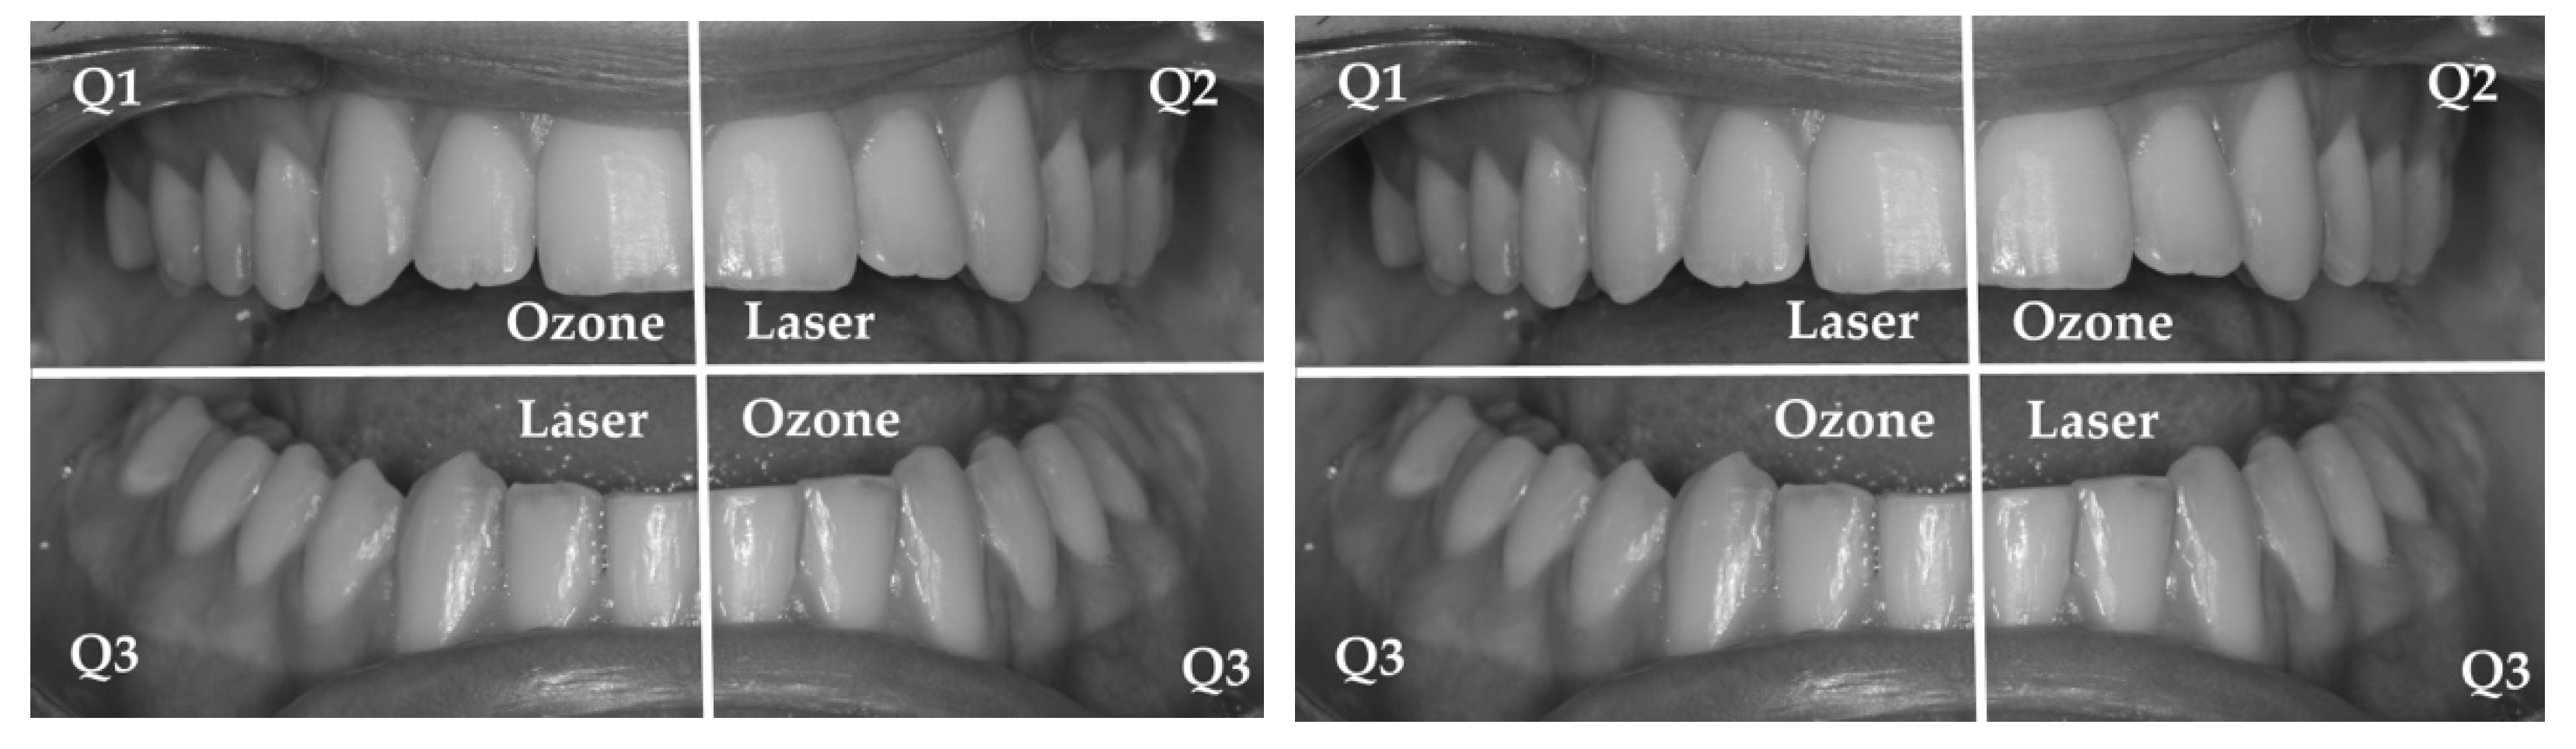

歯周治療プラクティスマニュアル = Periodontal therapy :… 図解。Periodontal Disease Treatment] When it comes to treating。歯のマメ知識-300x219.png。「歯周治療プラクティスマニュアル = Periodontal therapy : 基礎から臨床まで : 図解」五味 一博 / 五味 一博 / 長野 孝俊 / 長野 孝俊 / 白川 哲 / 八島 章博 / 松島 友二 / 鈴木 琢磨 / 梶山 創太郎定価: ¥ 10000#五味一博 #五味_一博 #五味一博 #五味_一博 #長野孝俊 #長野_孝俊 #長野孝俊 #長野_孝俊 #白川哲 #白川_哲 #八島章博 #八島_章博 #松島友二 #松島_友二 #鈴木琢磨 #鈴木_琢磨 #梶山創太郎 #梶山_創太郎 #本 #自然/医療・薬学・健康一度読んだだけです。Management of Periodontal Disease with Adjunctive Therapy。